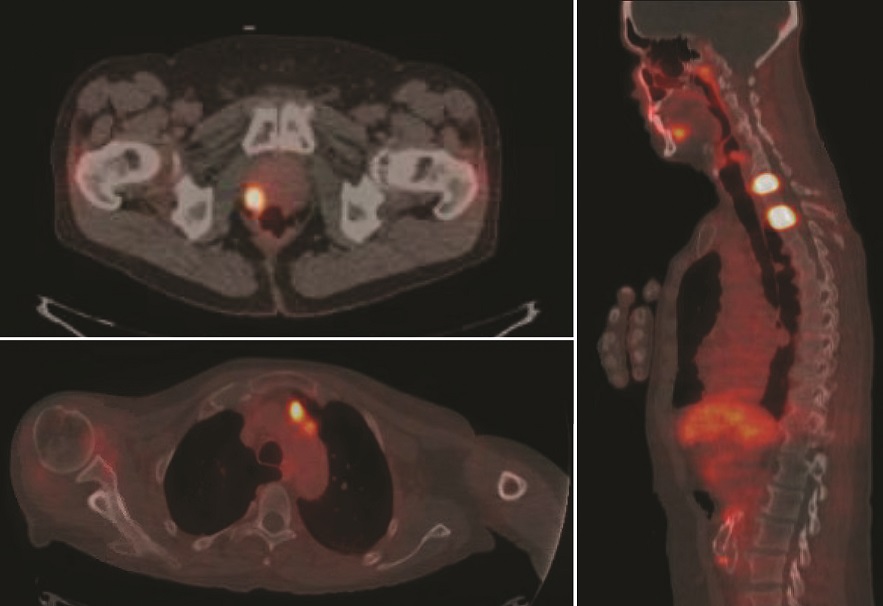

Ridley-Tree’s Nuclear Medicine Department is now using a radioactive agent called PYLARIFY® (F18-PSMA) to provide more accurate and earlier detection of prostate cancer than our previous imaging methods. This diagnostic tracer, approved by the FDA in May 2021, helps physicians in two scenarios: 1) when a patient is newly diagnosed and the physicians want maximum information about the prostate cancer’s location before treatment, and 2) when a patient who was previously treated for prostate cancer has a blood test that suggests cancer has returned.

Plarify x-ray

F18-PSMA / PET-CT imaging has greatly advanced how urologists and oncologists can view prostate cancer metastases and how they stage the disease. In patients with an elevated prostate specific antigen (PSA), Pylarify® was able to detect the location of the recurrent disease in nearly 2 out of 3 patients, when the disease was undetectable by prior imaging methods.